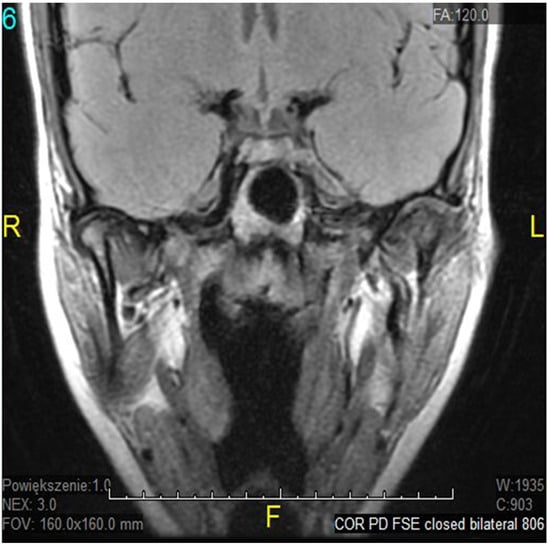

- Litko-Rola, M.; Szkutnik, J.; Różyło-Kalinowska, I. The importance of multisection sagittal and coronal magnetic resonance imaging evaluation in the assessment of temporomandibular joint disc position. Clin. Oral Investig. 2021, 25, 159–168. [Google Scholar] [CrossRef]